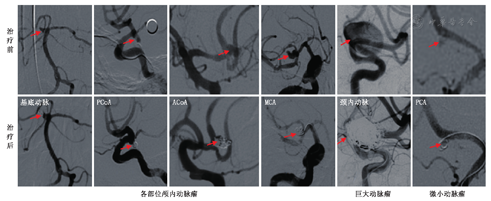

DSA是在脑血管中(动脉和静脉均可)注射造影剂,然后进行系统处理,使血管显示地更加清晰,便于医生诊断或进行手术。DSA所需的造影剂量少、浓度低、X线吸收量少,而对比度分辨率高,可展现脑部所有血管(颈内动脉系统和椎动脉系统)不同部位、不同狭窄程度的管腔及不同部位、不同大小的动脉瘤等(图10,图11),是脑血管病变检查的"金标准"。

PCoA:后交通动脉;ACoA:前交通动脉;MCA:大脑中动脉;PCA:大脑后动脉

DSA可用于各种目的的脑血管检查,包括脑血管病的病因检查,如颈部血管和脑血管狭窄、动脉瘤、动脉夹层(图12)、静脉血栓形成、动静脉瘘等;急诊动脉取栓、动脉溶栓以及脑动脉狭窄支架的介入治疗。